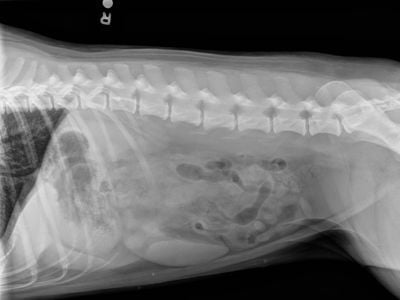

- Abdominal X-rays

Rehydration and restoring electrolyte balance are key factors in treating gastroenteritis. Preventive Vet dog Clover, in the photo above, is getting IV fluids after vomiting for over 24 hours. She was diagnosed with mild gastroenteritis.